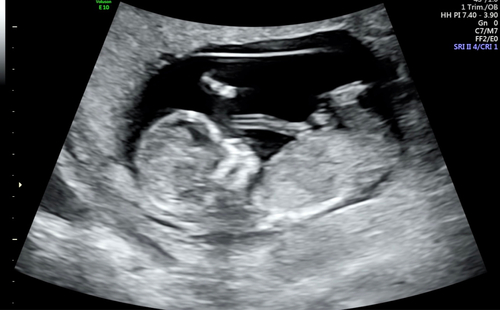

willen jullie met me mee kijken wat denken jullie dat het word ? 💙🩷❤️

11 weken 3dagen heb 2 foto's geplaatst vind je de andere ook een meisje?

Ja maar met deze termijn is dat heel normaal en kan het dus nog omhoog gaan en een alsnog een jongen blijken…